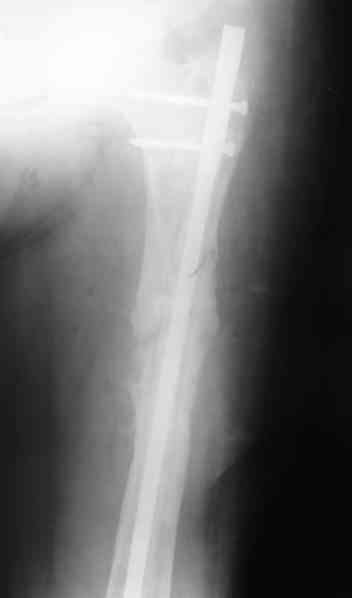

4, 5, 6 - рентгенограммы бедра и фотографии пациентки (прошу прощения за низкое качество рентгеновских снимков) от 7 сентября 2007 г.

В качестве демонстрации лечения канального остеомиелита бедренной кости представляем пациентку (см. parts 2 и 3), которая как раз сегодня была у нас на контрольном осмотре. В мае этого года мы произвели ей фиксацию бедренной кости штифтом-спейсером по поводу ложного сустава и канального остеомиелита бедренной кости. Через 4 недели после операции свищи закрылись. Сейчас она ходит с полной нагрузкой на конечность.